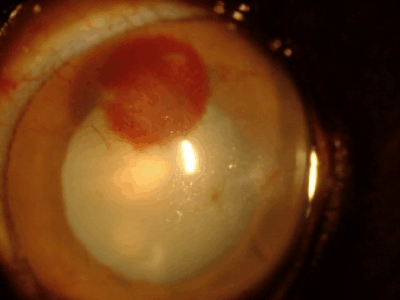

黒目が赤い場合

血管新生

・パンヌス

角膜には本来血管がなく透明ですが、炎症、傷、刺激などが慢性化すると角膜周囲から血管が伸びてきます。だいたい1日あたり1mm伸びるといわれています。原因としては角膜炎、角膜潰瘍、乾性角結膜炎(ドライアイ)、パンヌスなどがあります。